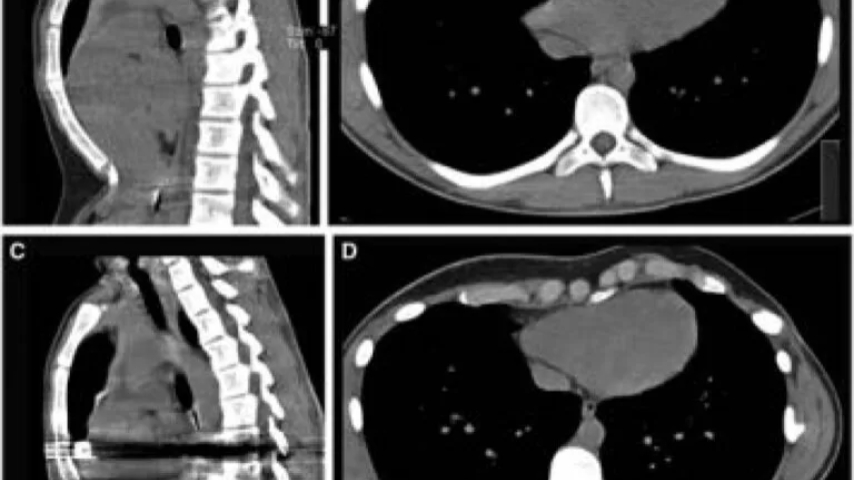

Arritmias ventriculares resueltas por corrección de pectus excavatum

Joven basketbolista en una ciudad de Portugal, es sometido a cirugía de corrección de pectus excavatum, como medida terapéutica de las arritmias ventriculares que padecía.